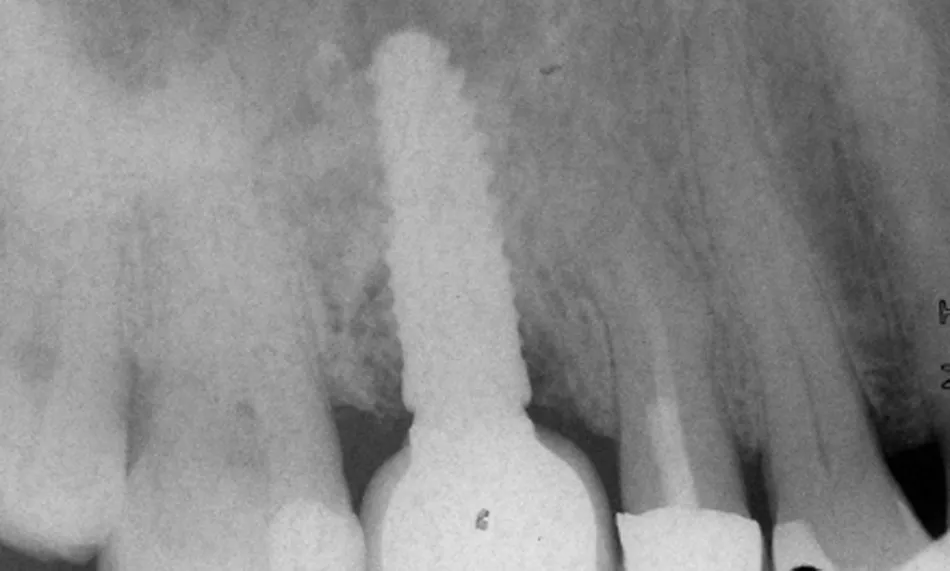

The original screw-retained prosthesis was reattached. The patient was enrolled in a 12-month follow-up program to monitor wound healing, tissue stability, and prosthetic function (Figs. 31–33).

Fig. 33

At the 12-month follow-up, the implant in region #16 showed healthy peri-implant tissues, with no signs of inflammation, bleeding on probing, or suppuration. Probing depths remained within normal limits, and radiographic evaluation confirmed stable marginal bone levels. The reinserted prosthesis worked without complications, and occlusal parameters remained stable. Both the patient and the clinician were highly satisfied with the outcome, particularly due to the resolution of symptoms, the preservation of the original prosthesis, and the regeneration of lost bone.